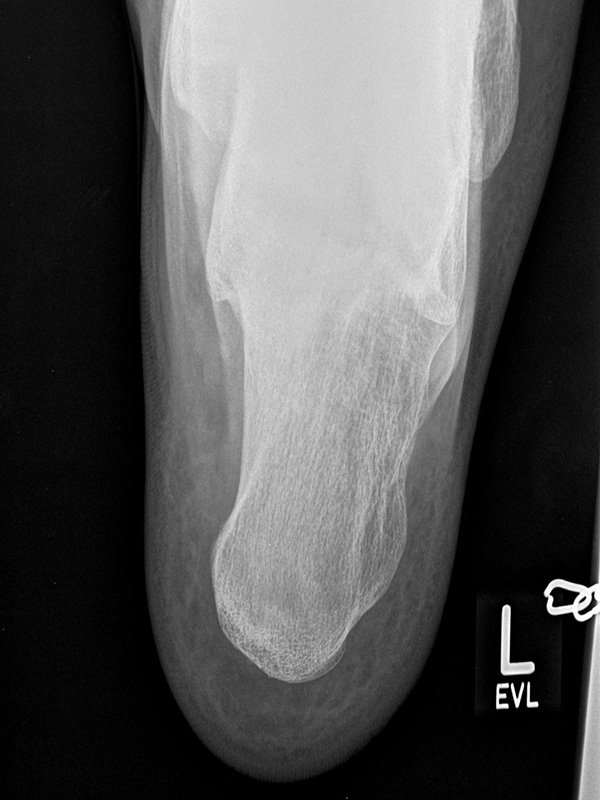

Stressaufnahme des oberen Sprunggelenks lateral

Position:

• Patient in Seitenlage auf dem Röntgentisch, zu untersuchender Fuß unten und seitlich auf der Röntgenkassette liegend (Achse des Fußes parallel zum Zentralstrahl).

• Zentralstrahl mittig auf das obere Sprunggelenk fokussiert.

• Film horizontal auf dem Röntgentisch.

• Röntgenröhre 0° vertikal.

• Der Fuß liegt in der Haltevorrichtung (z.B. Telos-Gerät, Scheuba-Apparat). Die Ferse wird von dorsal stabilisiert.

• Von ventral wird über die Tibia ein kontrollierter Druck von bis zu 15 daN (Dekanewton, entspricht ca. 15 kg) aufgebaut.

Kennzeichen des Röntgenbildes:

• Laterale Abbildung des oberen Sprunggelenks.

• Beurteilung der Translokation des Talus nach ventral (Talusvorschub).

• Gemessen wird die Verschiebung der Tibiaachse gegenüber der Talusachse.

• Als pathologisch gelten Talusvorschub > 2 mm im Seitenvergleich oder absoluter Talusvorschub > 4 mm.

Besondere Bemerkungen zum Beispielbild:

• Abbildung des oberen Sprunggelenks lateral.

• Fremdkörper in den plantaren Weichteilen in Höhe der plantaren Begrenzung des Kalkaneus.